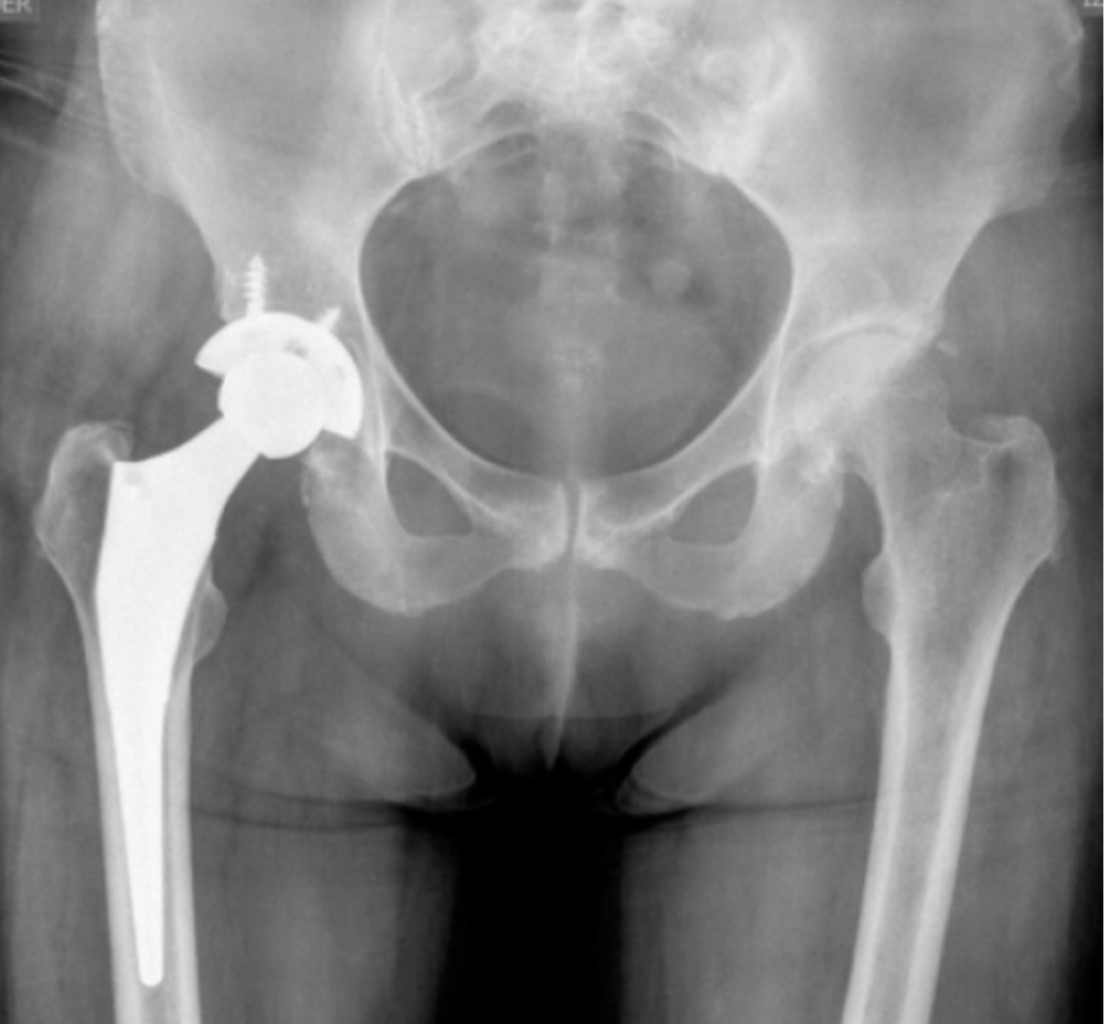

Alkaptonuria: evolution and course of the disease towards ochronotic arthropathy. Series of cases managed with joint replacement

Introduction: alkaptonuria is a very rare metabolic disease with autosomal recessive inheritance due to HGA oxidase deficiency. Classically described and diagnosed in the third to fourth decade of life, affecting both men and women; Its diagnostic impression is clinical based on the blue/black coloration of the conjunctivae, however it is confirmed by the specific analysis of the enzyme in the urine, to date there is no cure and its treatment is palliative and symptomatic. Material and methods: descriptive, observational, case series study, the primary objective of which is to describe the progression of the disease and its involvement in the musculoskeletal system. Results: two clinical cases are presented in women and men in which the broad clinic is illustrated, its progressive advance and the different alterations that it can generate in the musculoskeletal system. Conclusions: alkaptonuria is a rare disease which leads to a severe secondary arthropathy, currently without a specific management which is based on treating the symptoms, in its final stages joint replacements are a management option with satisfactory results for the relief of pain.

Figure 1

Figure 2

Figure 3

Figure 4

Figure 5

Figure 6

Figure 7

Figure 8

Figure 9